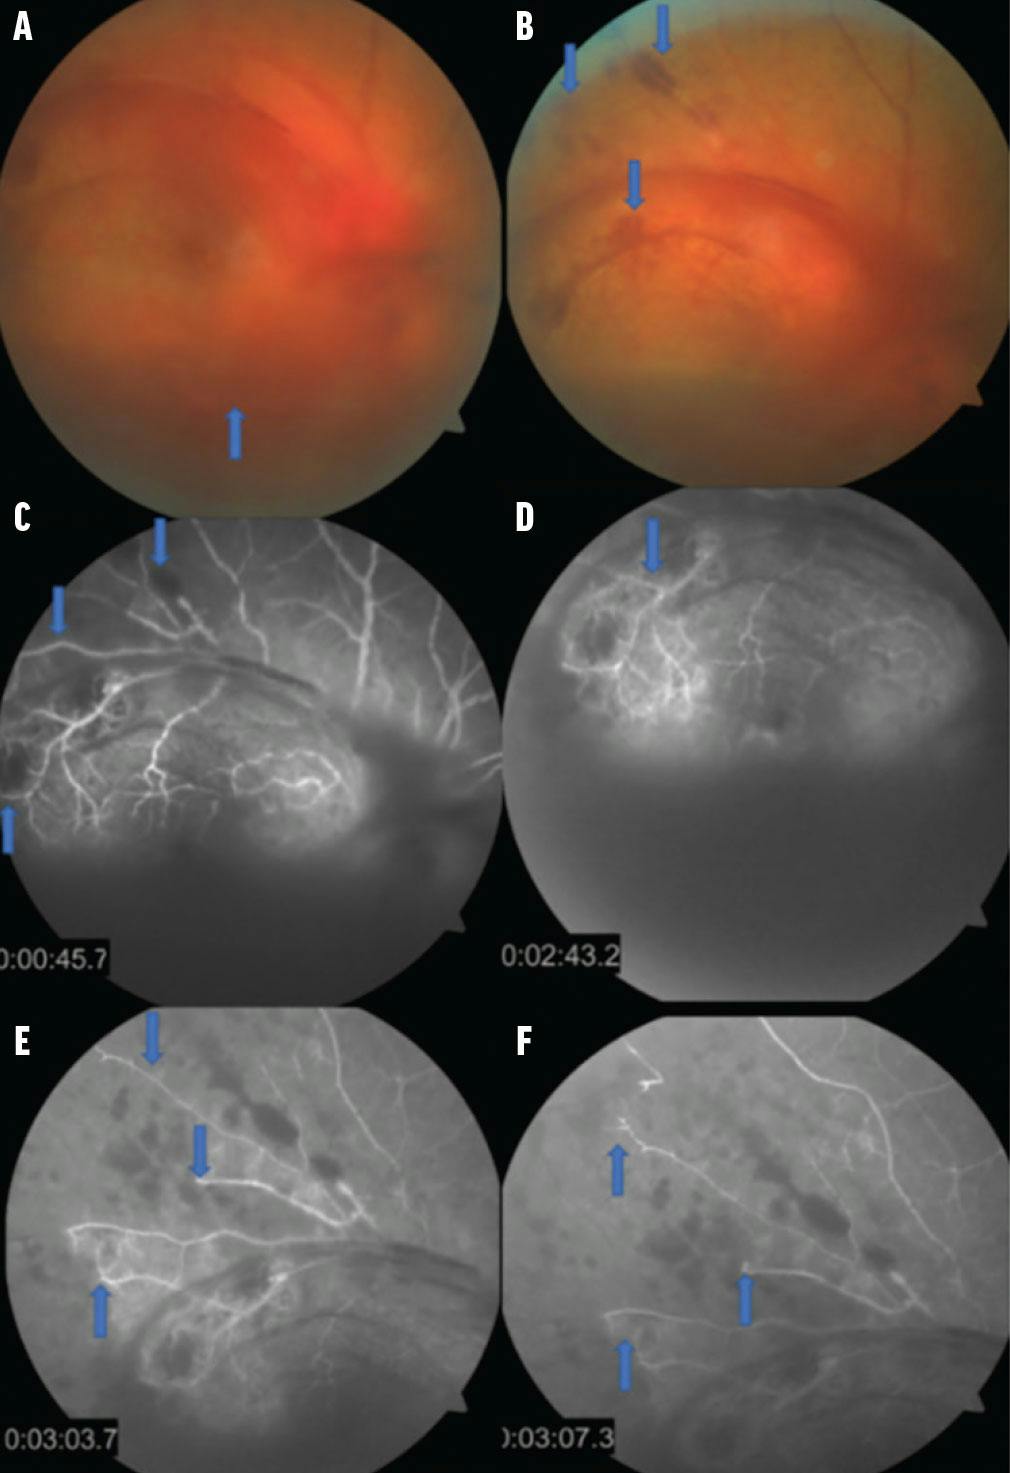

Fluorescein angiography of the right eye demonstrated severe vascular occlusion that was predominantly ischemic with neovascularization and vitreous hemorrhage. These findings prompted a diagnosis of retinal ischemia secondary to mixed vascular occlusion (Figure 1).

Figure 1. Color fundus photographs of the right eye showed vitreous hemorrhage and retinal and preretinal hemorrhage (A, B). Fluorescein angiography of the right eye showed hyperfluorescence due to a peripheral filling defect (C, D). Vascular changes were noted with areas of hyperfluorescence due to staining in the arterial phase and areas of hypoperfusion due to a filling defect toward the late phases of the angiographic study on arcades and in relation to the mixed vascular occlusion (E, F).